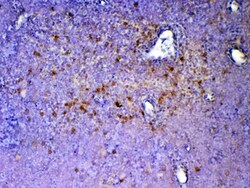

Reconstitute with 0.2 mL of distilled water to yield a concentration of 500 μg/mL. Positive Control - WB: mouse stomach tissue, mouse spleen tissue, mouse thymus tissue, mouse small intestine tissue, rat thymus tissue, human placenta tissue. IHC: mouse spleen tissue, mouse thymus tissue, rat spleen tissue.

| ELISA, Immunohistochemistry (Paraffin), Western Blot | |